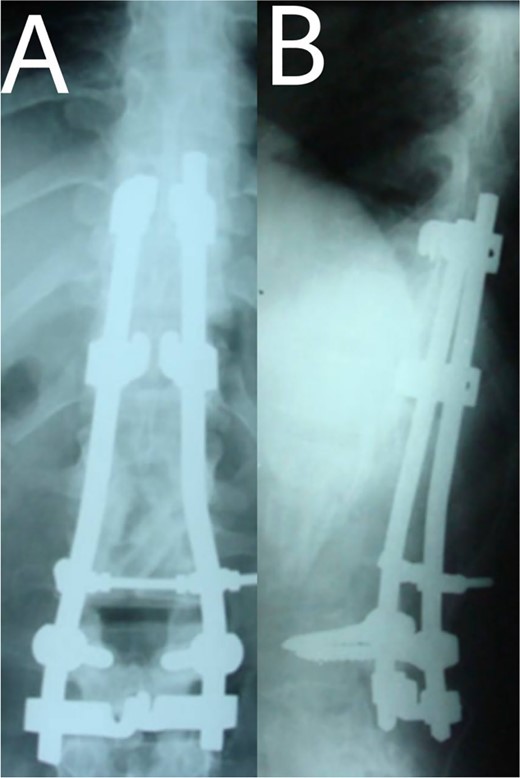

A 24-year-old farmer female was admitted to the Department of Neurosurgery with low back pain, no fever, cough, motor deficit, or any symptoms. Medical, surgical, family histories and physical examinations were unremarkable. The laboratory findings showed a white cell count of 9.8 × 103/μL, C-reactive protein concentrations of 20, erythrocyte sedimentation rate of 50 mm/1 h, 90 mm/2 h and tuberculin skin test was positive. X-ray films showed the collapse of the L1, L2 vertebrae, and L1–2 intervertebral space (Fig. 1). An abscess was observed at the L1–L2 vertebral level in lumbar magnetic resonance imaging (MRI) (Fig. 2). Chest X-rays and Sputum smear were negative. The patient was treated with anti-TB treatment (Isoniazid, Rifampicin, Ethambutol, Pyrazinamide) due to spinal TB findings on MRI (Fig. 3). After 40 days, the patient was diagnosed with grade 1/5 lower limb weakness, and bladder and bowel dysfunction, with no impairment in sensation, which predicts spinal infection. MRI confirmed these abnormalities and showed typical findings such as vertebral endplate destruction, bone marrow and disk signal abnormalities, and paravertebral or epidural abscesses (Fig. 3). Due to clinical manifestations and MRI spinal TB findings (Fig. 3), the patient underwent surgical debridement, interbody fusion and internal fixation with fibular autografting and supplemental posterior spinal stabilisation using a posterior-only approach. On post-operative follow-up, the treatment continued for 9 months, in addition to physical therapy for lower limb weakness. In the end, the patient returned to full motion with grade 5/5 in the lower limb, normal sensation, and no bladder or bowel incontinence. No recurrence was observed in the grafting area. Radiologically 2, 6 and 12 months, 14 years’ post-operation, the patient had achieved full bony graft spinal fusion (Figs 4–6).

(A, B) Post-operation, anteroposterior and lateral view showing fibular autograft implantation followed by supplemental posterior instrumentation.

(A, B) 2, 4 months after single-stage posterior extensive debridement and fibular autograft implantation followed by supplemental posterior instrumentation performed to treat the spinal infection.